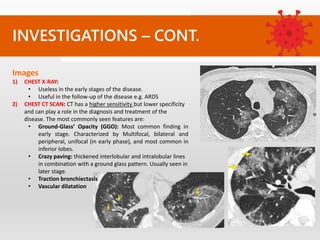

Images

1) CHEST X-RAY:

• Useless in the early stages of the disease.

• Useful in the follow-up of the disease e.g. ARDS

2) CHEST CT SCAN: CT has a higher sensitivity but lower specificity

and can play a role in the diagnosis and treatment of the

disease. The most commonly seen features are:

• Ground-Glass’ Opacity (GGO): Most common finding in

early stage. Characterized by Multifocal, bilateral and

peripheral, unifocal (in early phase), and most common in

inferior lobes.

• Crazy paving: thickened interlobular and intralobular lines

in combination with a ground glass pattern. Usually seen in

later stage.

• Traction bronchiectasis

• Vascular dilatation